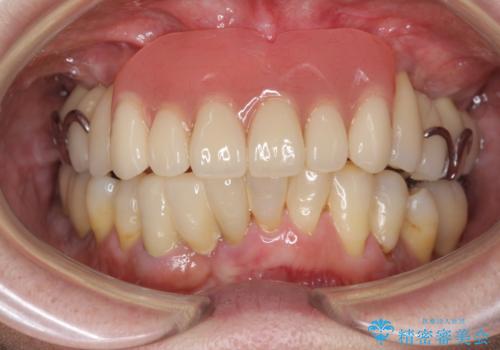

[ 重度歯周病 ] インプラント・義歯による咬合再構築

![[ 重度歯周病 ] インプラント・義歯による咬合再構築の症例 治療後](https://seimitsushinbi.jp/wp/wp-content/uploads/2021/07/4c6838854beaf5801dbc7fde26492d6c-500x350.jpg?v=1626759531)